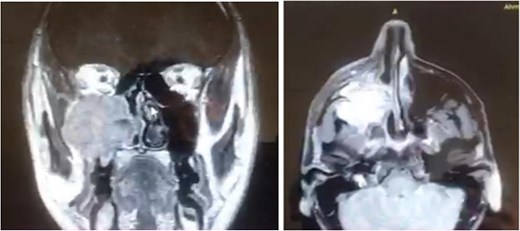

A 42-year-old male previously diagnosed with maxillary nasal sinus squamous cell carcinoma (SCC) was hospitalized for surgical treatment of recurrent infiltrating AC. The patient experienced three recurrences with the initial treatment approach for the cancer as SCC, a non-keratinizing variant. Complete excision and curettage of the lining mucosa were performed. In the second recurrence, the patient underwent additional curettage and subsequently revealed the absence of tumor residues from the mucosa and submucosa. However, the patient experienced a third recurrence with rapid growth and infiltration to the floor of the right maxillary sinus, filling the sinus space, infratemporal fossa, pterygopalatine fossa, cheek buccal area, and orbital floor. The imaging studies were preformed revealing a neoplastic lesion centered on the right maxillary sinus measuring 10 × 5 × 4.5 cm with a low T1 signal, heterogeneous iso T2/STIR signal, and intense heterogeneous post-contrast enhancement (Fig. 1). AC was recognized as stage II based on Yang’s et al. classification system [6]. Right Subtotal maxillectomy was performed through a Weber Ferguson incision with a Dieffenbach extension, and the infiltration areas were cleared. The excised tumor mass from the right maxillary sinus with labeled surgical margins (palate, orbital floor, buccal, and pterygoid surgical margins) was subjected to permanent paraffin evaluation (Fig. 2). The Right hemi-maxillectomy measuring 6 × 4.5 × 4 cm, revealed one canine, two molars, and two premolars found in the alveolar arch. An indefinite, grayish-white, infiltrating, fungating mass, approximately (⁓6 × 4 × 2.5 cm), was observed in the maxillary sinus. The cut surface of the mass was grayish-white and firm, with skeletal muscle attachment and noticeable infiltration into the underlying periosteum of the alveolar arch. Furthermore, labeled tumor tissue fragments measuring 4.7 × 2 × 2.5 cm and multiple smaller pieces collectively measuring 4 × 4 × 2 cm, showing similar characteristics, were stored in the same container. Microscopic examinations were performed at different magnifications. At a low magnification, the specimen revealed the presence of an infiltrative tumor with a biphasic pattern. The Islands and epithelial cell sheets are embedded in the fibrous stroma. The tumor islands exhibited a basaloid appearance with peripheral palisading, reverse polarity, and central stellate reticulum-like cells, reminiscent of ameloblastoma. However, these neoplastic epithelial cells exhibited moderate cytological atypia and increased mitotic activity, which suggests of malignancy (Fig. 3). Higher magnification shows tumor cells with enlarged, pleomorphic nuclei, prominent nucleoli, and eosinophilic cytoplasm. Frequent mitotic figures, including atypical forms, were also observed. Peripherally, tumor islands comprise cells with hyperchromatic elongated nuclei exhibiting focal palisading. The central cells were loosely cohesive and exhibited a stellate reticulum-like morphology. Additionally, focal areas of necrosis, hemorrhage, and keratinization were prominent in the tumor islands, and the surrounding stroma appeared desmoplastic and encompassed moderate chronic inflammatory infiltrates (Fig. 4). Additionally, diffuse infiltration of tumor into the adjacent tissues was observed, including bone and soft tissues, and is associated with perineural and lymphovascular invasion. Tumor extension in the orbital floor and buccal mucosal surgical margins was evident. In contrast, the palatal and pterygoid surgical margins are free of tumor involvement (Fig. 5). Overall, the morphological features were consistent with a diagnosis of infiltrating AC. Furthermore, immunohistochemistry assay was performed using a Ventana BenchMark GX Auto-stainer, employing the Ventana I View DAB detection system and Ventana monoclonal antibodies. The sections were stained for CK 5/6, P63, CK19, SOX-2, SOX-10, calretinin, and Ki67. The results revealed that the tumor basaloid epithelial component was strongly positive for P63 and showed weak heterogeneous positive staining for CK19, calretinin, and SOX-2 (Fig. 6). Conversely, it was negative for CK5/6 and SOX-10 staining. The Ki67 labeled index within the epithelial component was ⁓14%, whereas the mesenchymal component was 8%. The post-operative radiotherapy at 66 Gy was successfully administered. The patient is currently under observation, with careful follow-up.

The excised ameloblastic tumor mass of the right maxillary sinus.